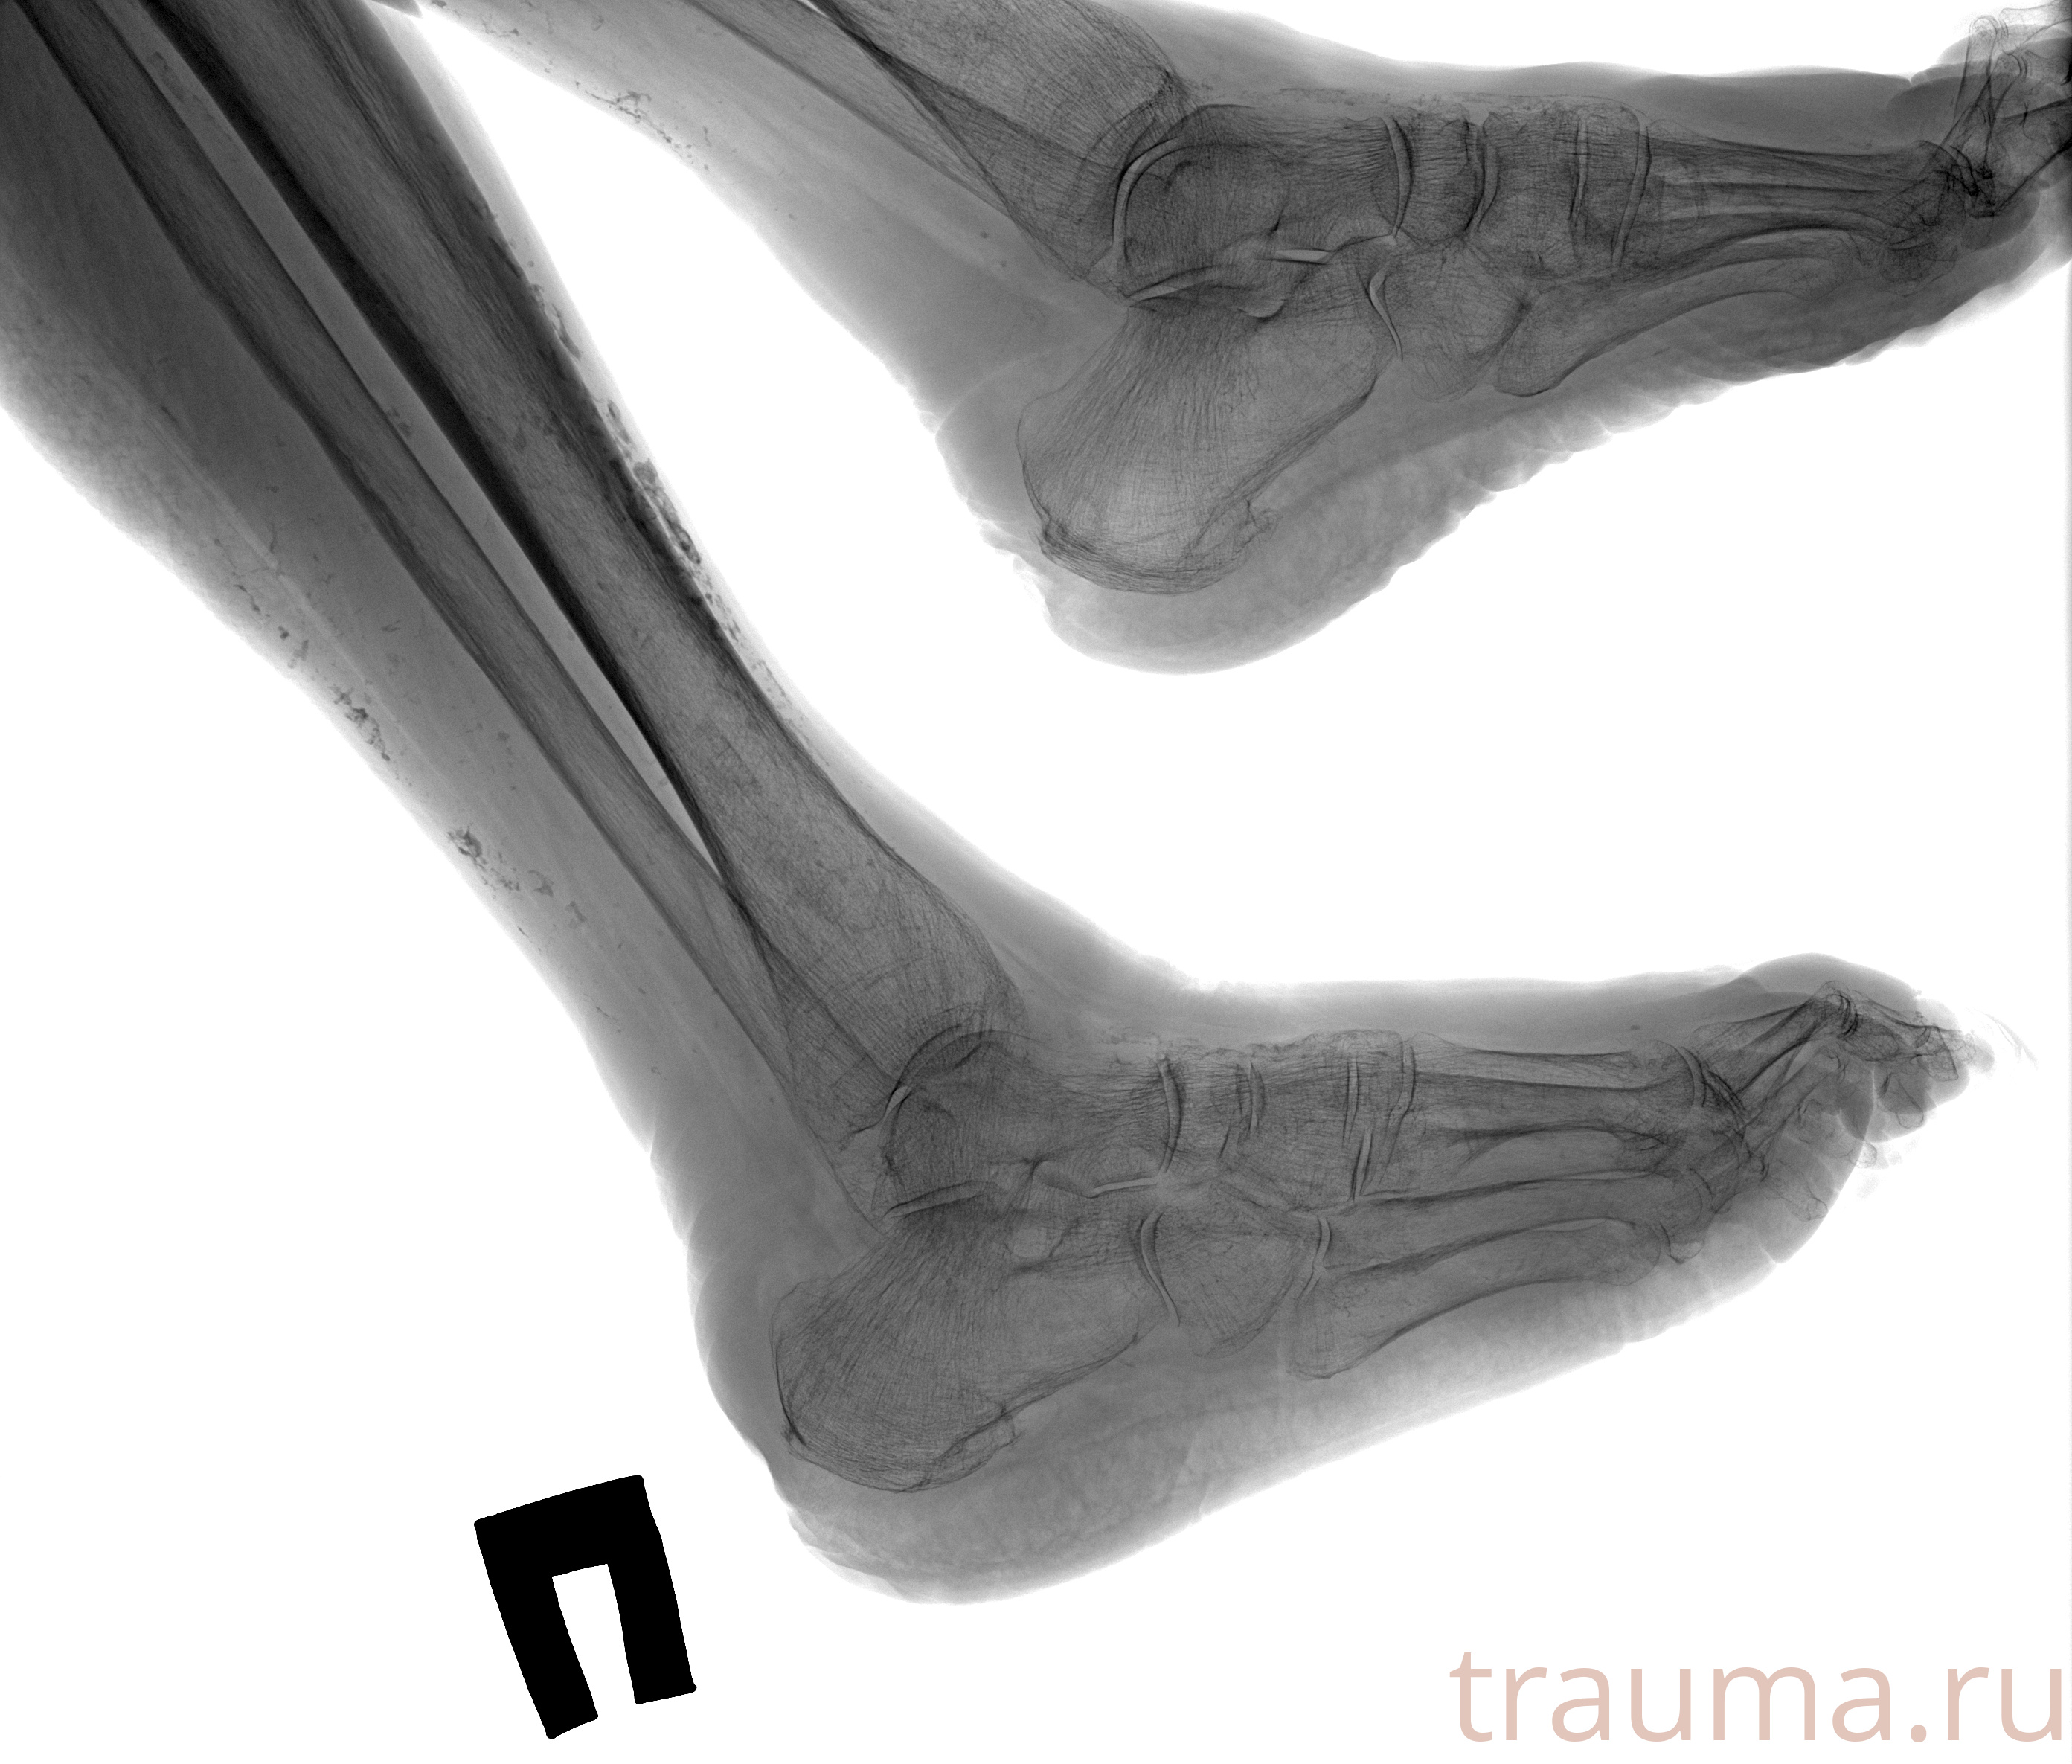

Рентгенограммы

Рентген на дому: по вашему адресу приезжает врач-рентгенолог, травматолог-ортопед с мобильным рентгеновским аппаратом, проводит диагностику травмы или заболевания, делает необходимые рентгенограммы, дает рекомендации по дальнейшему лечению. Получить качественные снимки в домашних условиях возможно благодаря уникальной методике, разработанной МосРентген Центром для института  Склифосовского